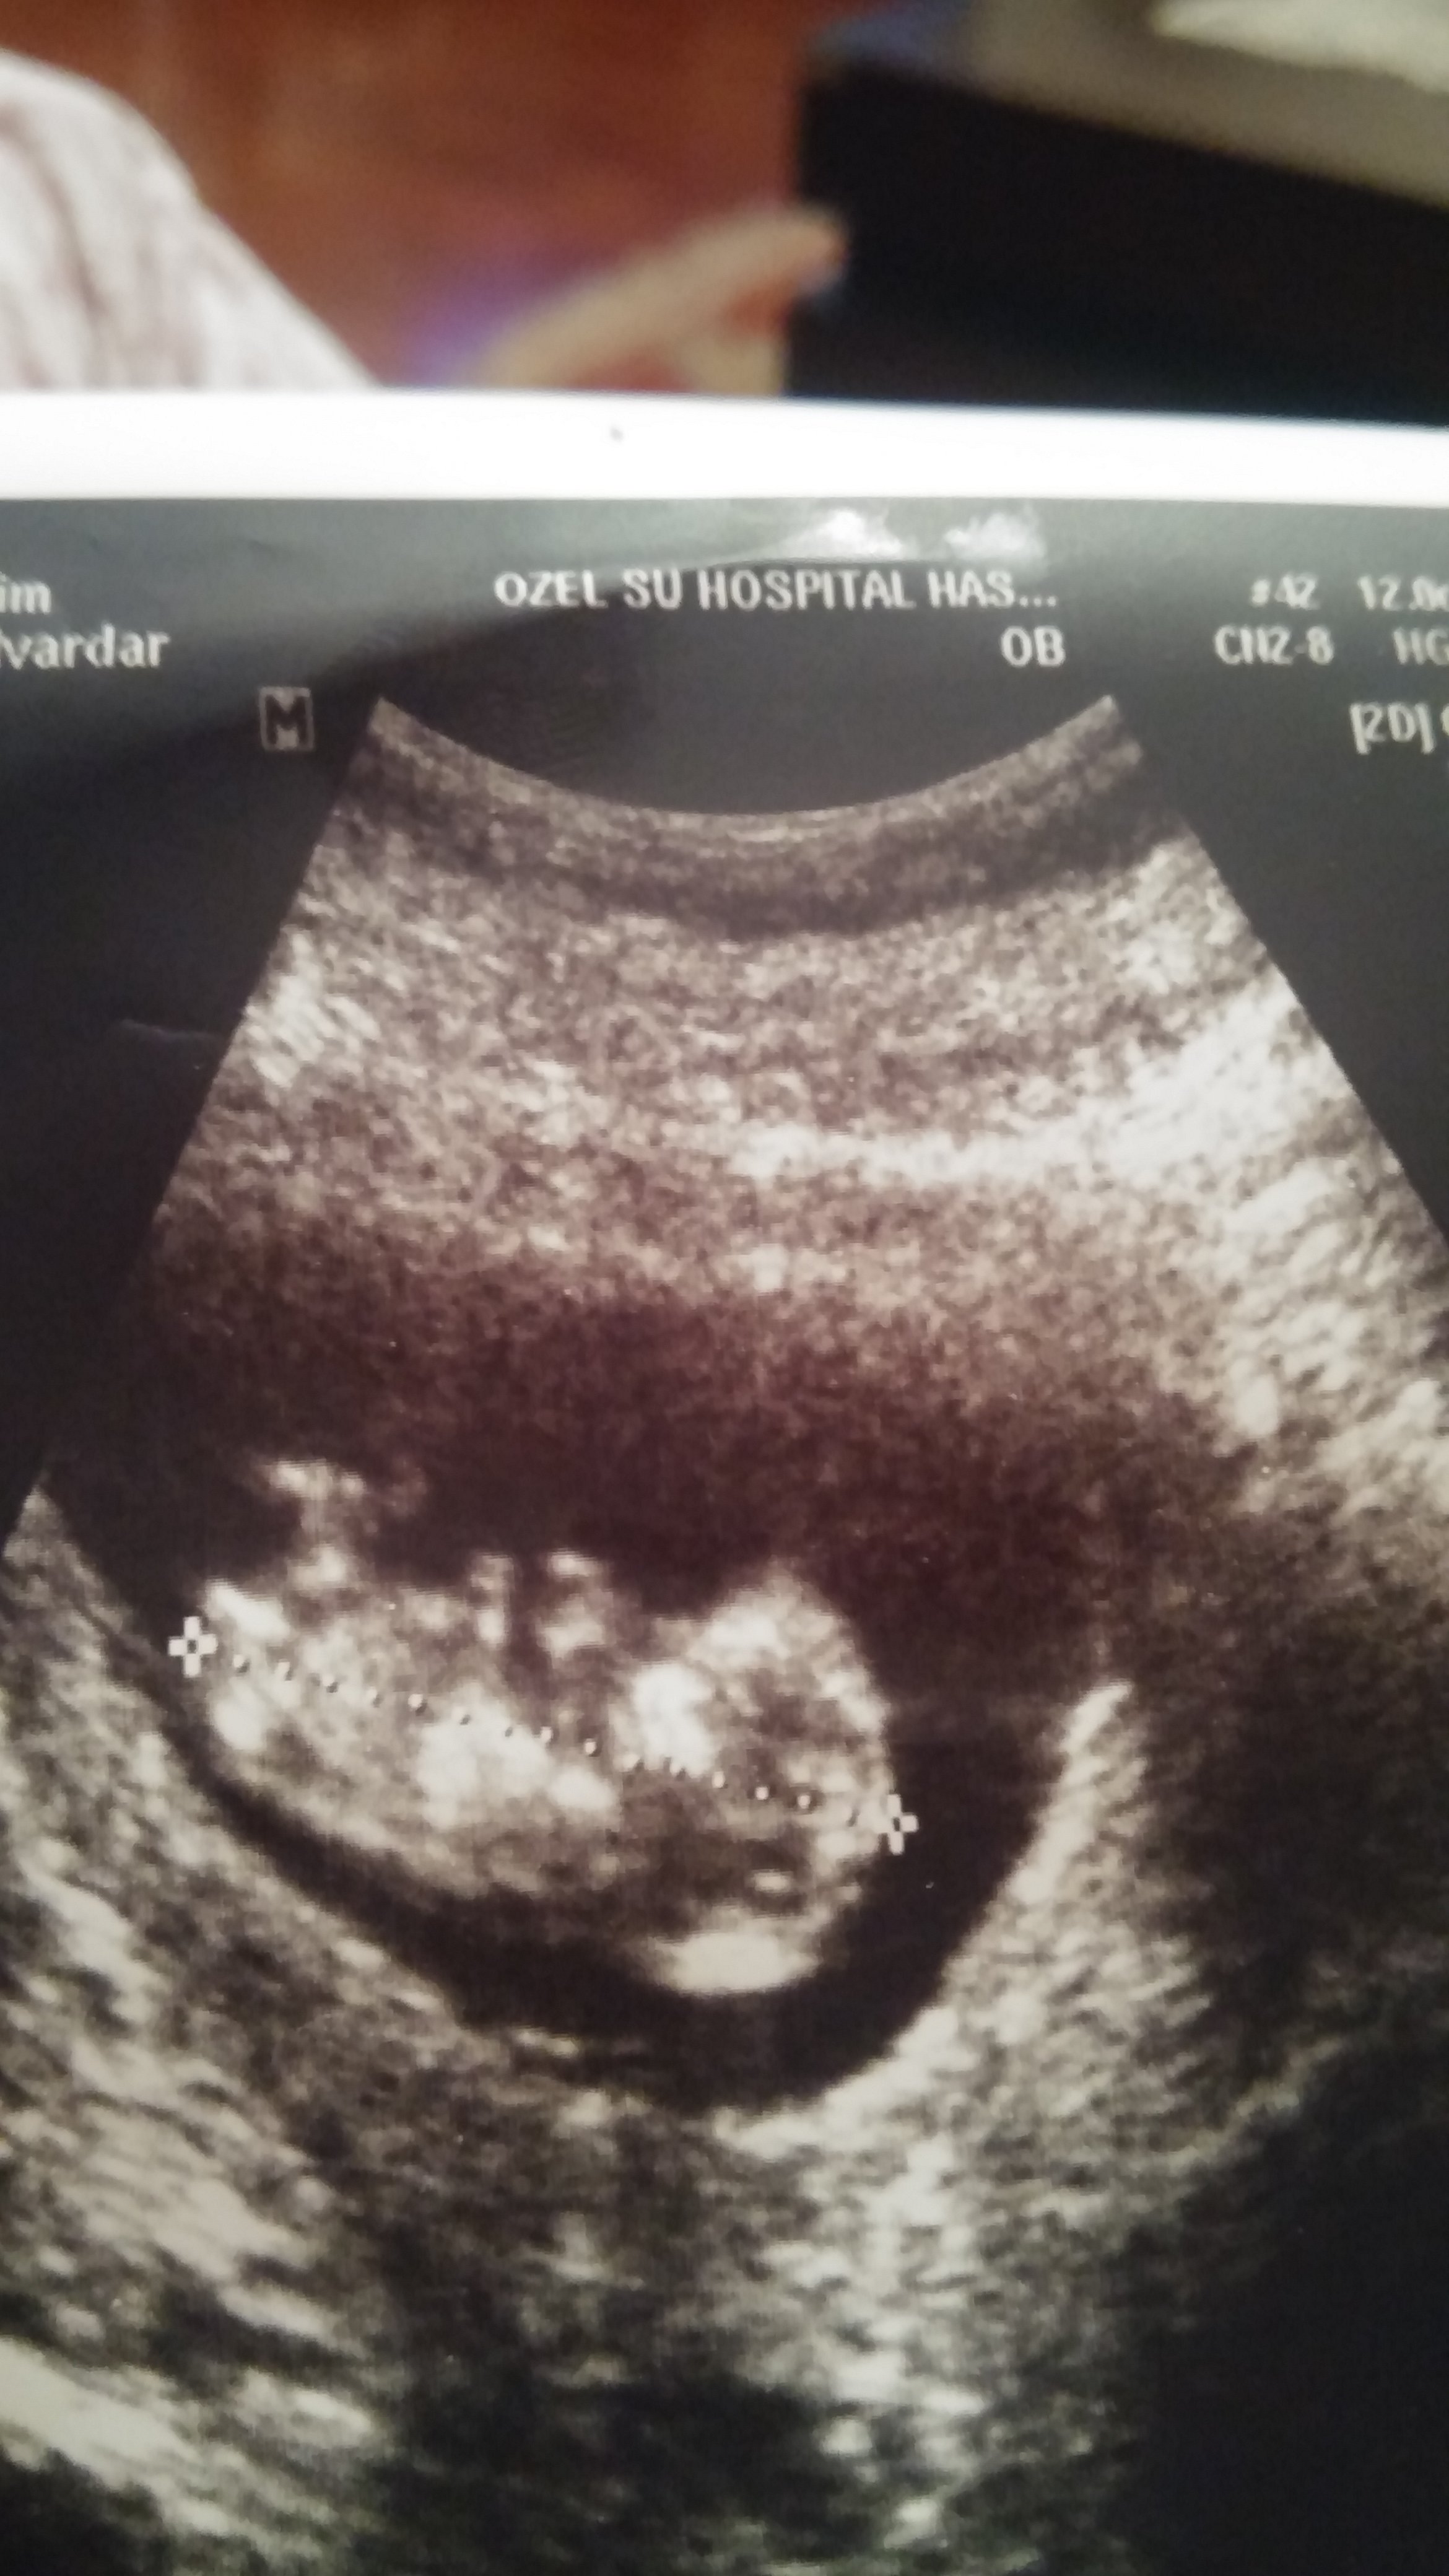

HemşireniZ Aktif Üye Üye 3 Ekim 2017 #357 Merhaba, yüklediğiniz görsel pek net değil. Bebeğinizin cinsiyeti emin olmamakla birlikte erkeğe benziyor..Sağlıklı gebelik geçirmeniz dileği ile.

Merhaba, yüklediğiniz görsel pek net değil. Bebeğinizin cinsiyeti emin olmamakla birlikte erkeğe benziyor..Sağlıklı gebelik geçirmeniz dileği ile.